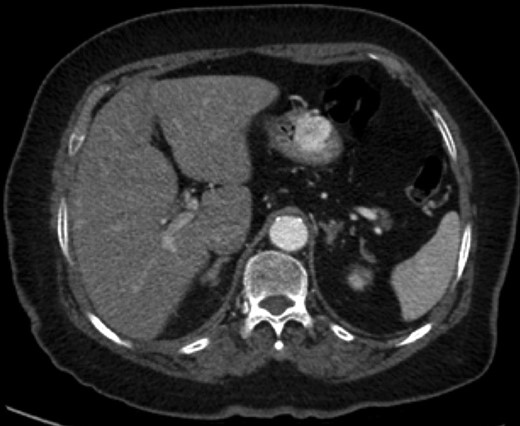

An 88-year-old female presented with 5 days of weakness and dyspnea, severe anemia (hemoglobin of 46 g/l), and no evidence of bleeding on history. Physical examination was remarkable for a blood pressure of 83/48, and black stool on rectal examination. Endoscopy demonstrated a 4-cm submucosal mass in the distal body of the stomach. The mass had central ulceration and a visible vessel, not actively bleeding. The presumptive diagnosis was GIST. CT demonstrated a 2.5 × 1.9 cm well-circumscribed, partially exophytic, arterially enhancing lesion. She underwent wedge resection of the greater curvature. She was discharged home on postoperative day 3 without complication. Pathology found a lobulated tumor composed of glomus cells in the submucosa and muscularis propria. The cells were positive for α-smooth muscle actin, caldesmon and vimentin. There was focal positivity for synaptophysin and CD34. These are consistent with a GT.

Endoscopic findings of gastric GTs are that of a submucosal mass, typically in the antrum or distal body, with either normal mucosa or ulceration [3, 4] (Fig. 1). CT shows a well-defined submucosal tumor with a clear margin, strong enhancement in the arterial phase, and prolonged enhancement in the delayed phase [4, 5] (Fig. 2). Often confused with GIST, the distinguishing features are that the density of GISTs is lower than that of GTs, and GISTs do not exhibit prolonged enhancement in the delayed phase [5]. On EUS, the GT is found in the fourth endosonographic layer, with a heterogeneous appearance. In one small study of seven gastric GTs, six demonstrated the characteristic ‘peripheral halo’ sign around the tumor [5].